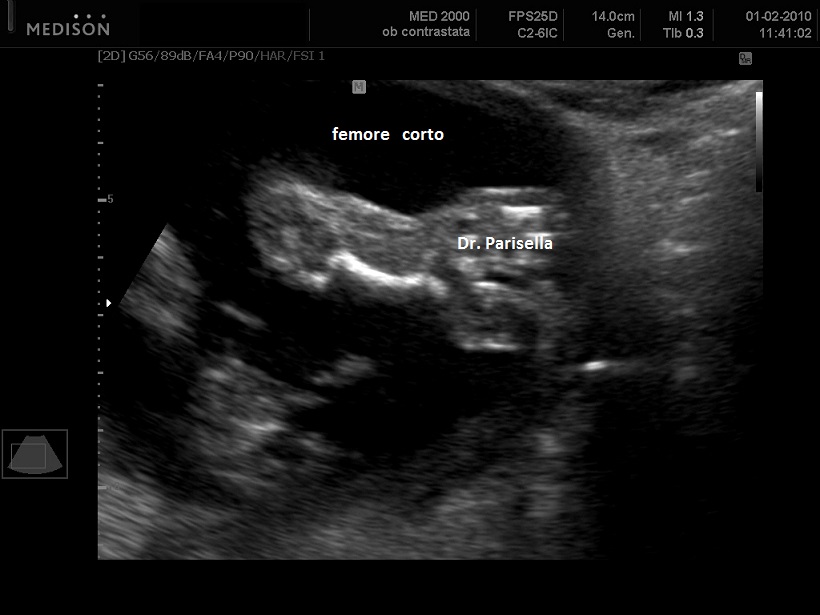

I segni sono: fragilità ossea, incurvamento delle ossa lunghe (specie femore), scoliosi, brevità degli arti (specie femore), contratture in flessione di gomiti e ginocchia. Possono essere presenti brachicefalia e micrognatia.